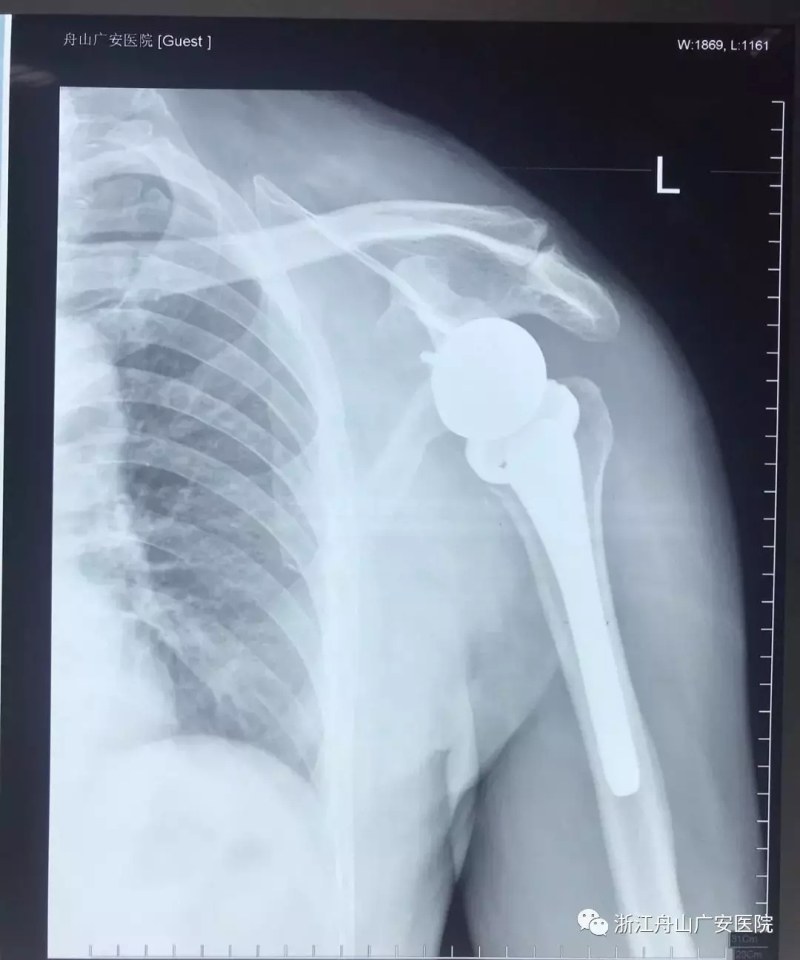

經(jīng)過術(shù)前精心的手術(shù)準(zhǔn)備,羅軍主任帶領(lǐng)手術(shù)專家團(tuán)隊(duì)為張大伯做了反式人工肩關(guān)節(jié)置換術(shù)。手術(shù)過程十分順利,僅用時(shí)一個(gè)半小時(shí),且手術(shù)刀口很小,約10cm,術(shù)后恢復(fù)快,第二天查房時(shí)候張大伯便能佩戴特制的肩肘墊起床活動(dòng),術(shù)前肩關(guān)節(jié)劇痛也大大緩解減輕,術(shù)后兩周患者功能恢復(fù)良好。

反式肩關(guān)節(jié)置換術(shù)后照片